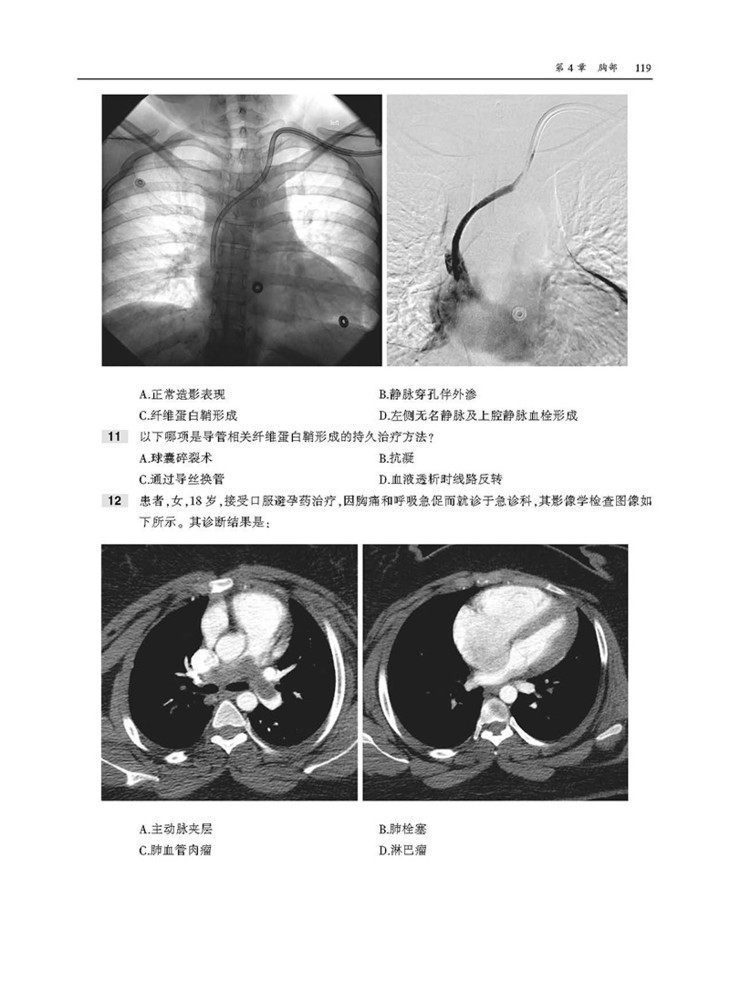

本书为“影像学核心复习系列丛书”之一,内容翔实,通过相关病例以及对应影像图,对血管介入放射学的内容进行了描述。本书囊括上百幅高清图像,直观展示病变要点。每章采取选择题形式,首先给出患者病史和影像图片,然后列出问题和选项,便于读者独立思考,选择答案。各章“答案与解析”部分不仅详细解释正确答案,而且说明错误选项的原因,此外,问题后还配有相关参考文献,有助于读者进一步扩展知识,有针对性地进行阅读和复习。

2. 直观性,本书按部位分别论述了胸部、胃肠道系统、泌尿系统、生殖内分泌系统的介入治疗,含百余幅高清图像,直观展示病变要点,是临床医师迫切需要并且手头缺乏的重要参考资料。